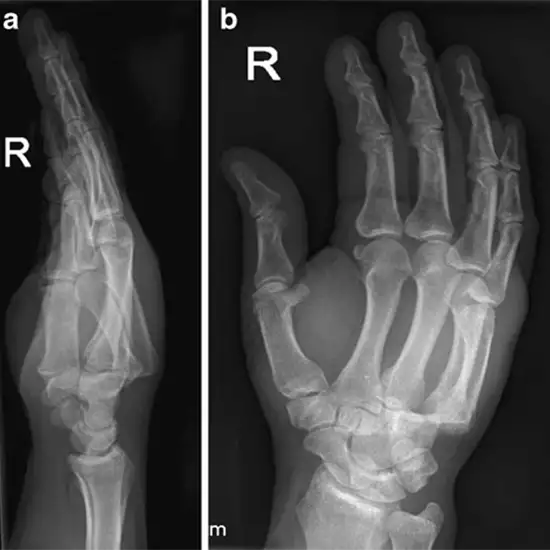

Radiograph Right Hand AP Views aid in visualizing the hands and their surroundings with a minimal quantity of radiation. The hand consists of wrist bones (carpal bones), bones between wrist bones and fingers (metacarpal bones), and fingers (phalanges). It is advised in the case of hand symptoms such as discomfort, tenderness, and swelling.

It aids in diagnosing infections, bone cysts, tumors, fractures, and osteomyelitis in the hand bones. Checking the alignment of bones after surgery or as part of a bone-age study is also recommended before undergoing surgery.